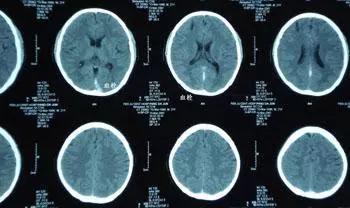

脑梗塞又叫中风,多发于动脉粥样硬化病症的患者,病人常伴有高血压病,动脉硬化,高血脂症,冠心病,糖尿病等慢性病,导致脑组织缺血、缺氧、坏死,引起神经功能障碍的一种脑血管病。

脑梗分为两种类型,出血型和缺血型。出血型的死亡率更高,接近50%的死亡率;缺血型也不容忽视,可达到30%~40%的死亡率。